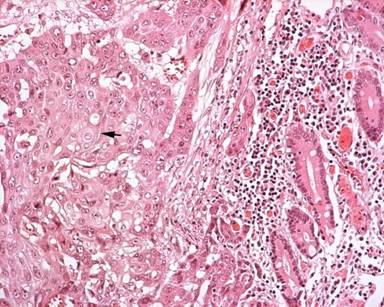

The macroscopic inspection of the resected specimen revealed a 5 cm, solid, whitish and ulcerated tumor originating from the ampulla of Vater and invading the pancreatic head through the duodenal wall (Figure 2). Histopathological examination showed a moderately differentiated squamous cell carcinoma. Multiple serial sections of the tumor specimen failed to detect an adenomatous component. Tumor cells were highly pleomorphic, arranged in solid nests or sheets with individual cell keratinization, intercellular bridges and well-formed keratin pearls (Figure 3). Immunohistochemical analysis showed that the tumor cells were positive for epithelial membrane antigen, pan-keratins and CEA but negative for cytokeratins 8, 18 and 19, S-100 protein, neuron specific enolase, chromogranin and ΗΜΒ45. Regional lymph nodes and resection margins were free of tumor and the disease was classified as stage IIA (T3N0M0) according to the sixth edition (2002) of the TNM system.

|

Figure 3. Microscopic appearance of a primary squamous cell carcinoma of the ampulla of Vater. Note keratinized cells with intercellular bridges (arrow). (H&E, original magnification x200). |